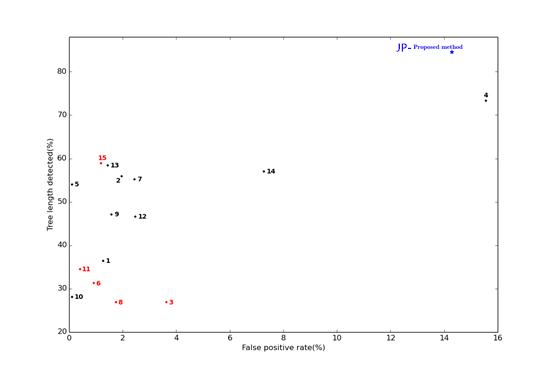

近期,健培AI團隊在全球EXACT’09(Extraction of Airways from CT , CT影像肺部氣管分割挑戰賽)的賽事中再創佳績,使氣管檢測長度達到了84.5%,超出現有成績10%以上,刷新了該項比賽的原有紀錄。來自韓國的Coreline Soft醫療團隊在氣管檢測長度上的結果為60.1%,健培以84.5%的成績遠優于該記錄。